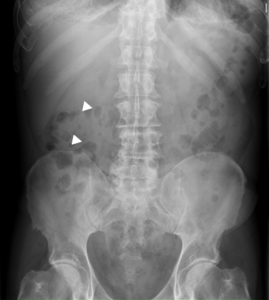

ABDOMINAL X-RAY

Inespecific. In advanced stages, a central mass of soft tissue at the level of the psoas line is sometimes seen.